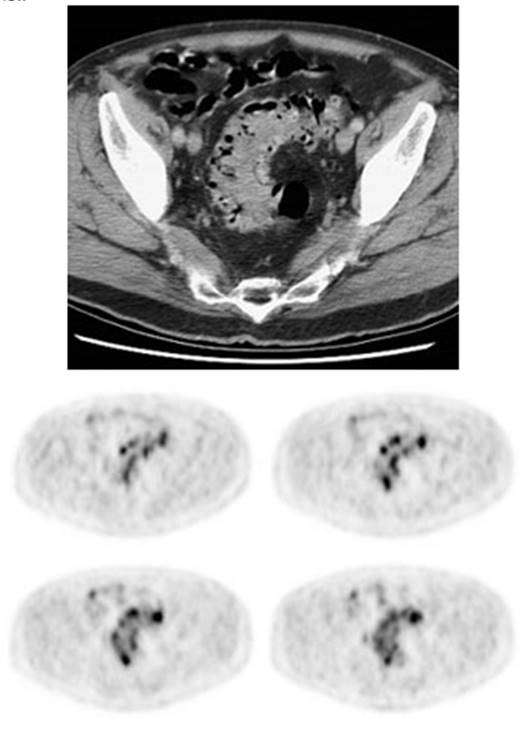

Figure 5 - Genitourinary activity: The image below demonstrates normal

renal and hepatic activity.

Figure 6 - Genitourinary activity: The image below

demonstrates activity within the collecting system of a transplanted kidney

(black arrows). This should not be mistaken for an abnormality.

Figure 7 - Bladder cancer: Despite urinary excretion

of the radiotracer, this patients bladder cancer

(white arrows) is readily identified on the PET scan (black arrows). In

general, however, urinary excretion of FDG limits evaluation of urinary tract

malignancy